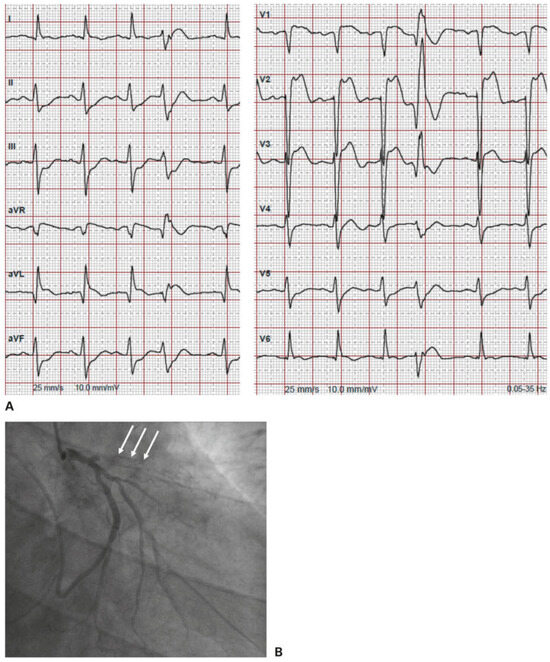

Familial hypercholesterolaemia: increasing physicians’ awareness in order to prevent early death. Familial hypercholesterolaemia (FH) is one of the most frequent autosomal dominant genetic conditions (1/200–300) and is still underdiagnosed and undert...